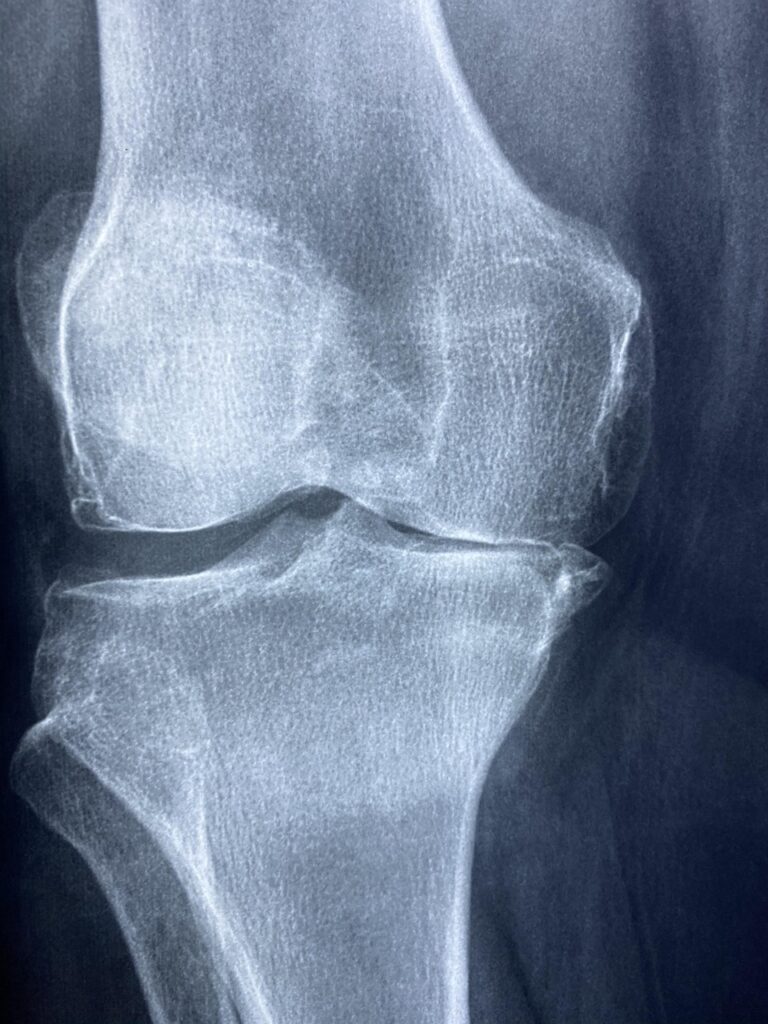

まず、膝の怪我が発生する主な原因について考えてみましょう。多くの場合、無理な動きや不適切なトレーニングが膝に過度な負担をかけます。例えば、急激な方向転換やジャンプ、着地の際に膝に大きなストレスがかかることがあります。これが膝の靭帯や軟骨にダメージを与え、痛みや障害を引き起こすことがあるのです。